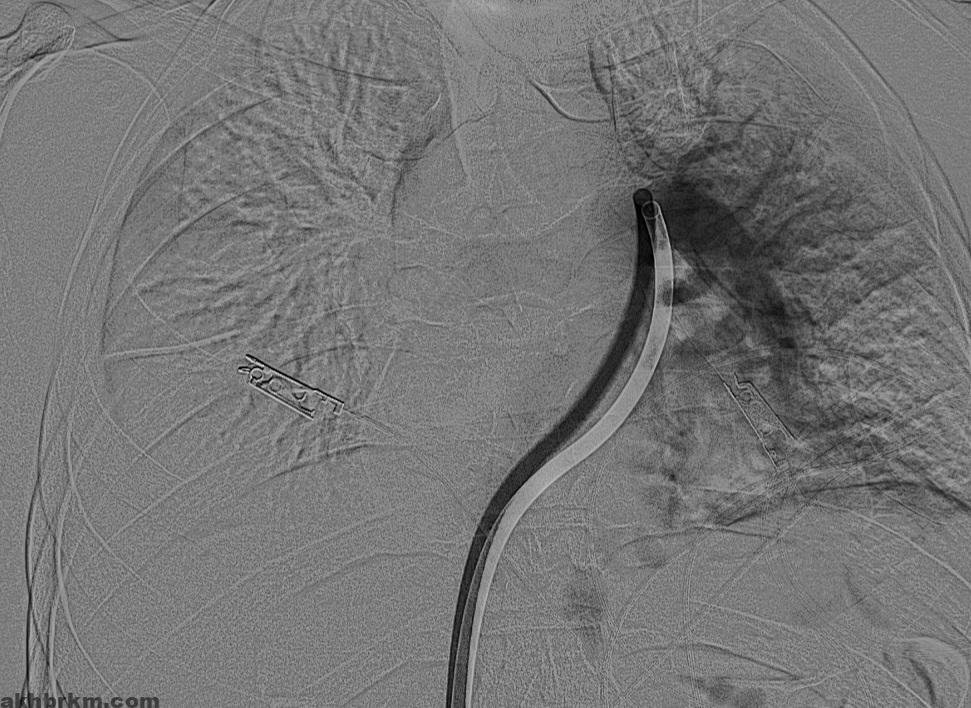

وكان المريض قد نُقل بشكل إسعافي من أحد المستشفيات وهو في حالة حرجة ، نتيجة معاناته من ضيق شديد في التنفس وانخفاض حاد في مستوى الأكسجين ، إثر انسداد كامل في الشريان الرئوي الرئيسي بسبب خثرات وريدية عميقة ظهرت بعد خضوعه لعملية منظار لمفصل الركبة.

وبفضل سرعة الاستجابة وجاهزية فريق الأشعة التداخلية جرى التدخل العلاجي العاجل وفتح الشريان الرئوي وسحب الجلطة بالكامل بدقة عالية ، ما أدى إلى تحسّن فوري في العلامات الحيوية واستقرار الحالة دون تسجيل أي مضاعفات.